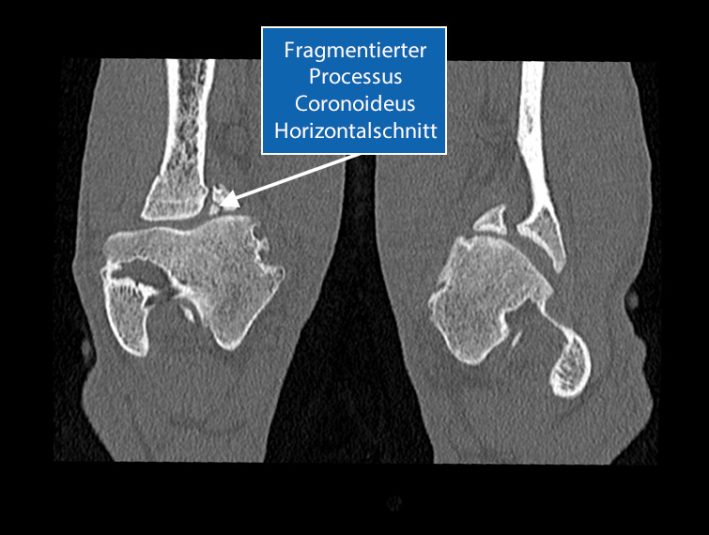

SLT Laengsschnitt Ellbogen ED FCP

Das abgebrochene Fragment (FCP) kann im weiteren Verlauf den Gelenksknorpel am Humerus condylus beschädigen, sodass der Knochen nicht mehr von einem Knorpel überzogen ist.